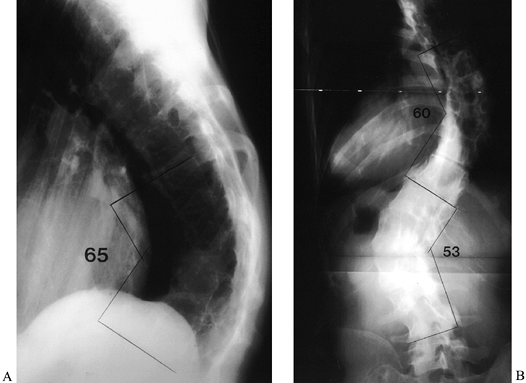

Figure 163.2. AP (A) and lateral (B) views of a 36-year-old woman with Marfan syndrome who presented 20 years after an in situ

thoracic fusion for scoliosis (T-6 to T-12). She had low-back pain,

progressive shoulder asymmetry, and progressive thoracic and lumbar

deformities. The lateral view shows a significant thoracolumbar

kyphosis, centered at T-9, which resulted in sagittal imbalance. The

thoracic fusion was substantial and solid. (From McLain RF. Revision

and Salvage in Deformity Surgery. Semin Spine Surg 1993;5:214, with permission.) -

Figure 163.5. Postoperative radiographs of patient in Figure 163.2.

After multiple osteotomies from T-6 to T-10, segmental instrumentation

was used to correct the double curve to less than 50% of the

preoperative deformity. Both sagittal and coronal deformities were

improved, and shoulder asymmetry was corrected. (From McLain RF.

Revision and Salvage in Deformity Surgery. Semin Spine Surg 1993;5:214, with permission.) -